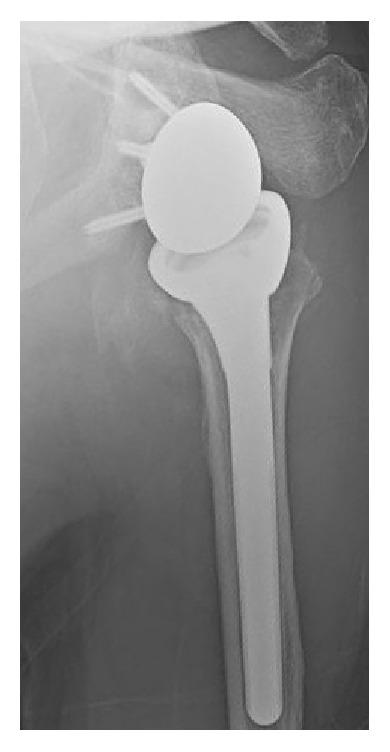

We report the case of a 70-year-old male with Parkinson's disease (PD) and recurrent traumatic left shoulder dislocations. This case is rare because (1) he had a massive irreparable rotator cuff tear and end-stage arthritis (i.e., rotator cuff-tear arthropathy) of the same shoulder and (2) his shoulder was ultimately reconstructed with a reverse total shoulder arthroplasty (RTSA). His first dislocation occurred after a fall. Recurrent shoulder dislocations occurred despite successful closed reduction and physical therapy. Initial surgical treatment included an open capsular-labral reconstruction; RTSA was not an ideal option because of the presumed risk of failure from PD-related dyskinesias. However, the capsular-labral reconstruction failed after he lost balance and stumbled but did not fall. A RTSA was then done which restored the patient's shoulder stability and greatly improved his pain. At final follow-up two years later, he reported pain relief and improved function. This was partially attributed to the fact that he had moved to an assisted living center. He also began using an electric wheelchair one year after the RTSA. We report this case because of the unusual set of conditions and circumstances, namely, the implantation of a RTSA in a patient with PD and shoulder instability.

我们报告了一例患有帕金森病(PD)且左侧肩部反复创伤性脱位的70岁男性病例。该病例较为罕见,原因如下:(1)他患有大面积不可修复的肩袖撕裂以及同一肩部的终末期关节炎(即肩袖撕裂性关节病);(2)其肩部最终通过反式全肩关节置换术(RTSA)进行了重建。他的首次脱位发生在一次跌倒后。尽管成功进行了闭合复位和物理治疗,但肩部仍反复脱位。初始手术治疗包括开放性关节囊盂唇重建;由于预计帕金森病相关运动障碍会导致手术失败风险,RTSA并非理想选择。然而,在他失去平衡绊倒但未摔倒后,关节囊盂唇重建失败。随后进行了RTSA,恢复了患者肩部的稳定性并极大地缓解了疼痛。在两年后的最终随访中,他报告疼痛减轻且功能改善。这部分归因于他已搬至辅助生活中心。在RTSA术后一年,他还开始使用电动轮椅。我们报告此病例是因为其一系列不寻常的情况,即在一名患有帕金森病且肩部不稳定的患者中植入了RTSA。